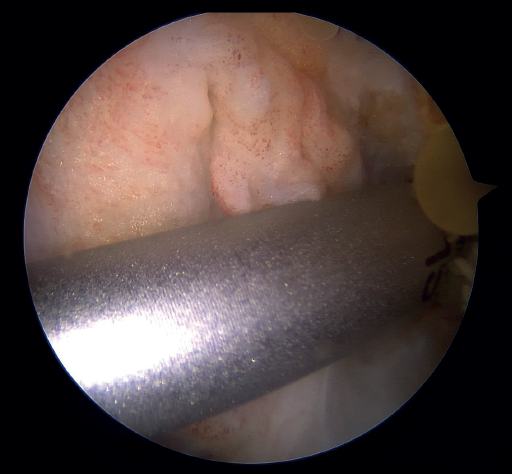

The next step consists of introducing the necessary instruments through the anteromedial portal to make several perforations approximately 1 mm deep in the femoral insertional footprint, with the aforementioned aim of obtaining a bleeding bed to facilitate healing of the ACL. Such drilling can be done manually (with micro- or nanofracture punches) or motorized (PowerPick®, Arthrex), and this step is usually made easier by flexing the knee at about 100°.

Once the bone marrow is stimulated, a short silicone cannula (PassPort®) is placed in the anteromedial portal with the help of vascular forceps. This cannula will help us to organize the suture threads and will make it difficult for Hoffa's fat pad and other soft tissues to get in the way. With the same aim of facilitating suture management (and drilling of the femoral tunnel), an accessory medial portal is now added, in a position medial to the anteromedial portal.